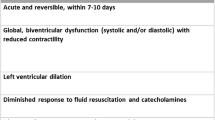

Acute cardiogenic pulmonary edema

Since their introduction in the clinical practice, compared to conventional oxygen therapy, the use of CPAP and, subsequently, NIV have clearly demonstrated superior beneficial effects in patients with acute cardiogenic pulmonary edema in terms of several cardiopulmonary physiological variables: these include a higher reduction of respiratory rate, respiratory work and dyspnea [106,107,108,109,110], increase in arterial oxygenation and in the ratio between PaO2 and the fraction of inspired O2 (PaO2/FiO2) [106, 107, 111, 112], decrease in PaCO2 together with an increase in pH [106, 107, 110, 112, 113], decrease in heart rate, in right and left ventricular preload and in blood pressure [106, 107, 109, 110, 113]. Most data seems to agree in indicating that CPAP and NIV have similar efficacy in improving pulmonary and cardiovascular function [109, 110, 113]. However, a few studies suggest that NIV could be more effective than CPAP in unloading respiratory muscles [109] and improving circulatory stress, dyspnea and gas exchange, particularly in patients with pulmonary edema and acidosis, and in reducing time to improvement in oxygenation [108, 114, 115]. The concern regarding the possible increase in the incidence of acute myocardial infarction with NIV compared to CPAP or standard oxygen therapy, initially raised by Mehta and coll. [108], was not confirmed in larger studies [110, 113, 115,116,117] and in several meta-analyses [92, 114, 118,119,120,121]. These results plead for the safety of these types of non-invasive ventilatory support in patients with acute cardiogenic pulmonary edema.